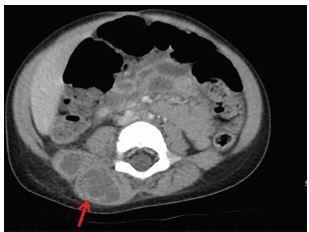

A paraspinal abscess is an uncommon condition frequently diagnosed late due to equivocal symptoms, which can lead to increased morbidity and mortality. Commonly associated risk factors include prior invasive spinal procedures, diabetes mellitus, trauma, chronic steroid use, malnutrition, intravenous drug use and an immunocompromised state. Pediatric paraspinal abscesses are not well documented in the literature. We report a case of a two-year-old female presenting with fevers, lower back pain, and decreased oral intake ultimately diagnosed with isolated lumbar paraspinal abscess. The patient underwent an ultrasound-guided percutaneous drainage of the abscess, subsequently improving, and was discharged within 48 hours of presentation.

椎旁脓肿是一种不常见的疾病,由于症状不明确,常常在晚期才得以诊断,这可能导致发病率和死亡率升高。常见的相关危险因素包括既往脊柱侵入性操作、糖尿病、创伤、长期使用类固醇、营养不良、静脉吸毒和免疫功能低下状态。小儿椎旁脓肿在文献中记载较少。我们报告一例两岁女性患儿,出现发热、下背部疼痛及经口摄入量减少,最终被诊断为孤立性腰椎椎旁脓肿。该患者接受了超声引导下脓肿经皮引流,随后病情改善,并在就诊后48小时内出院。